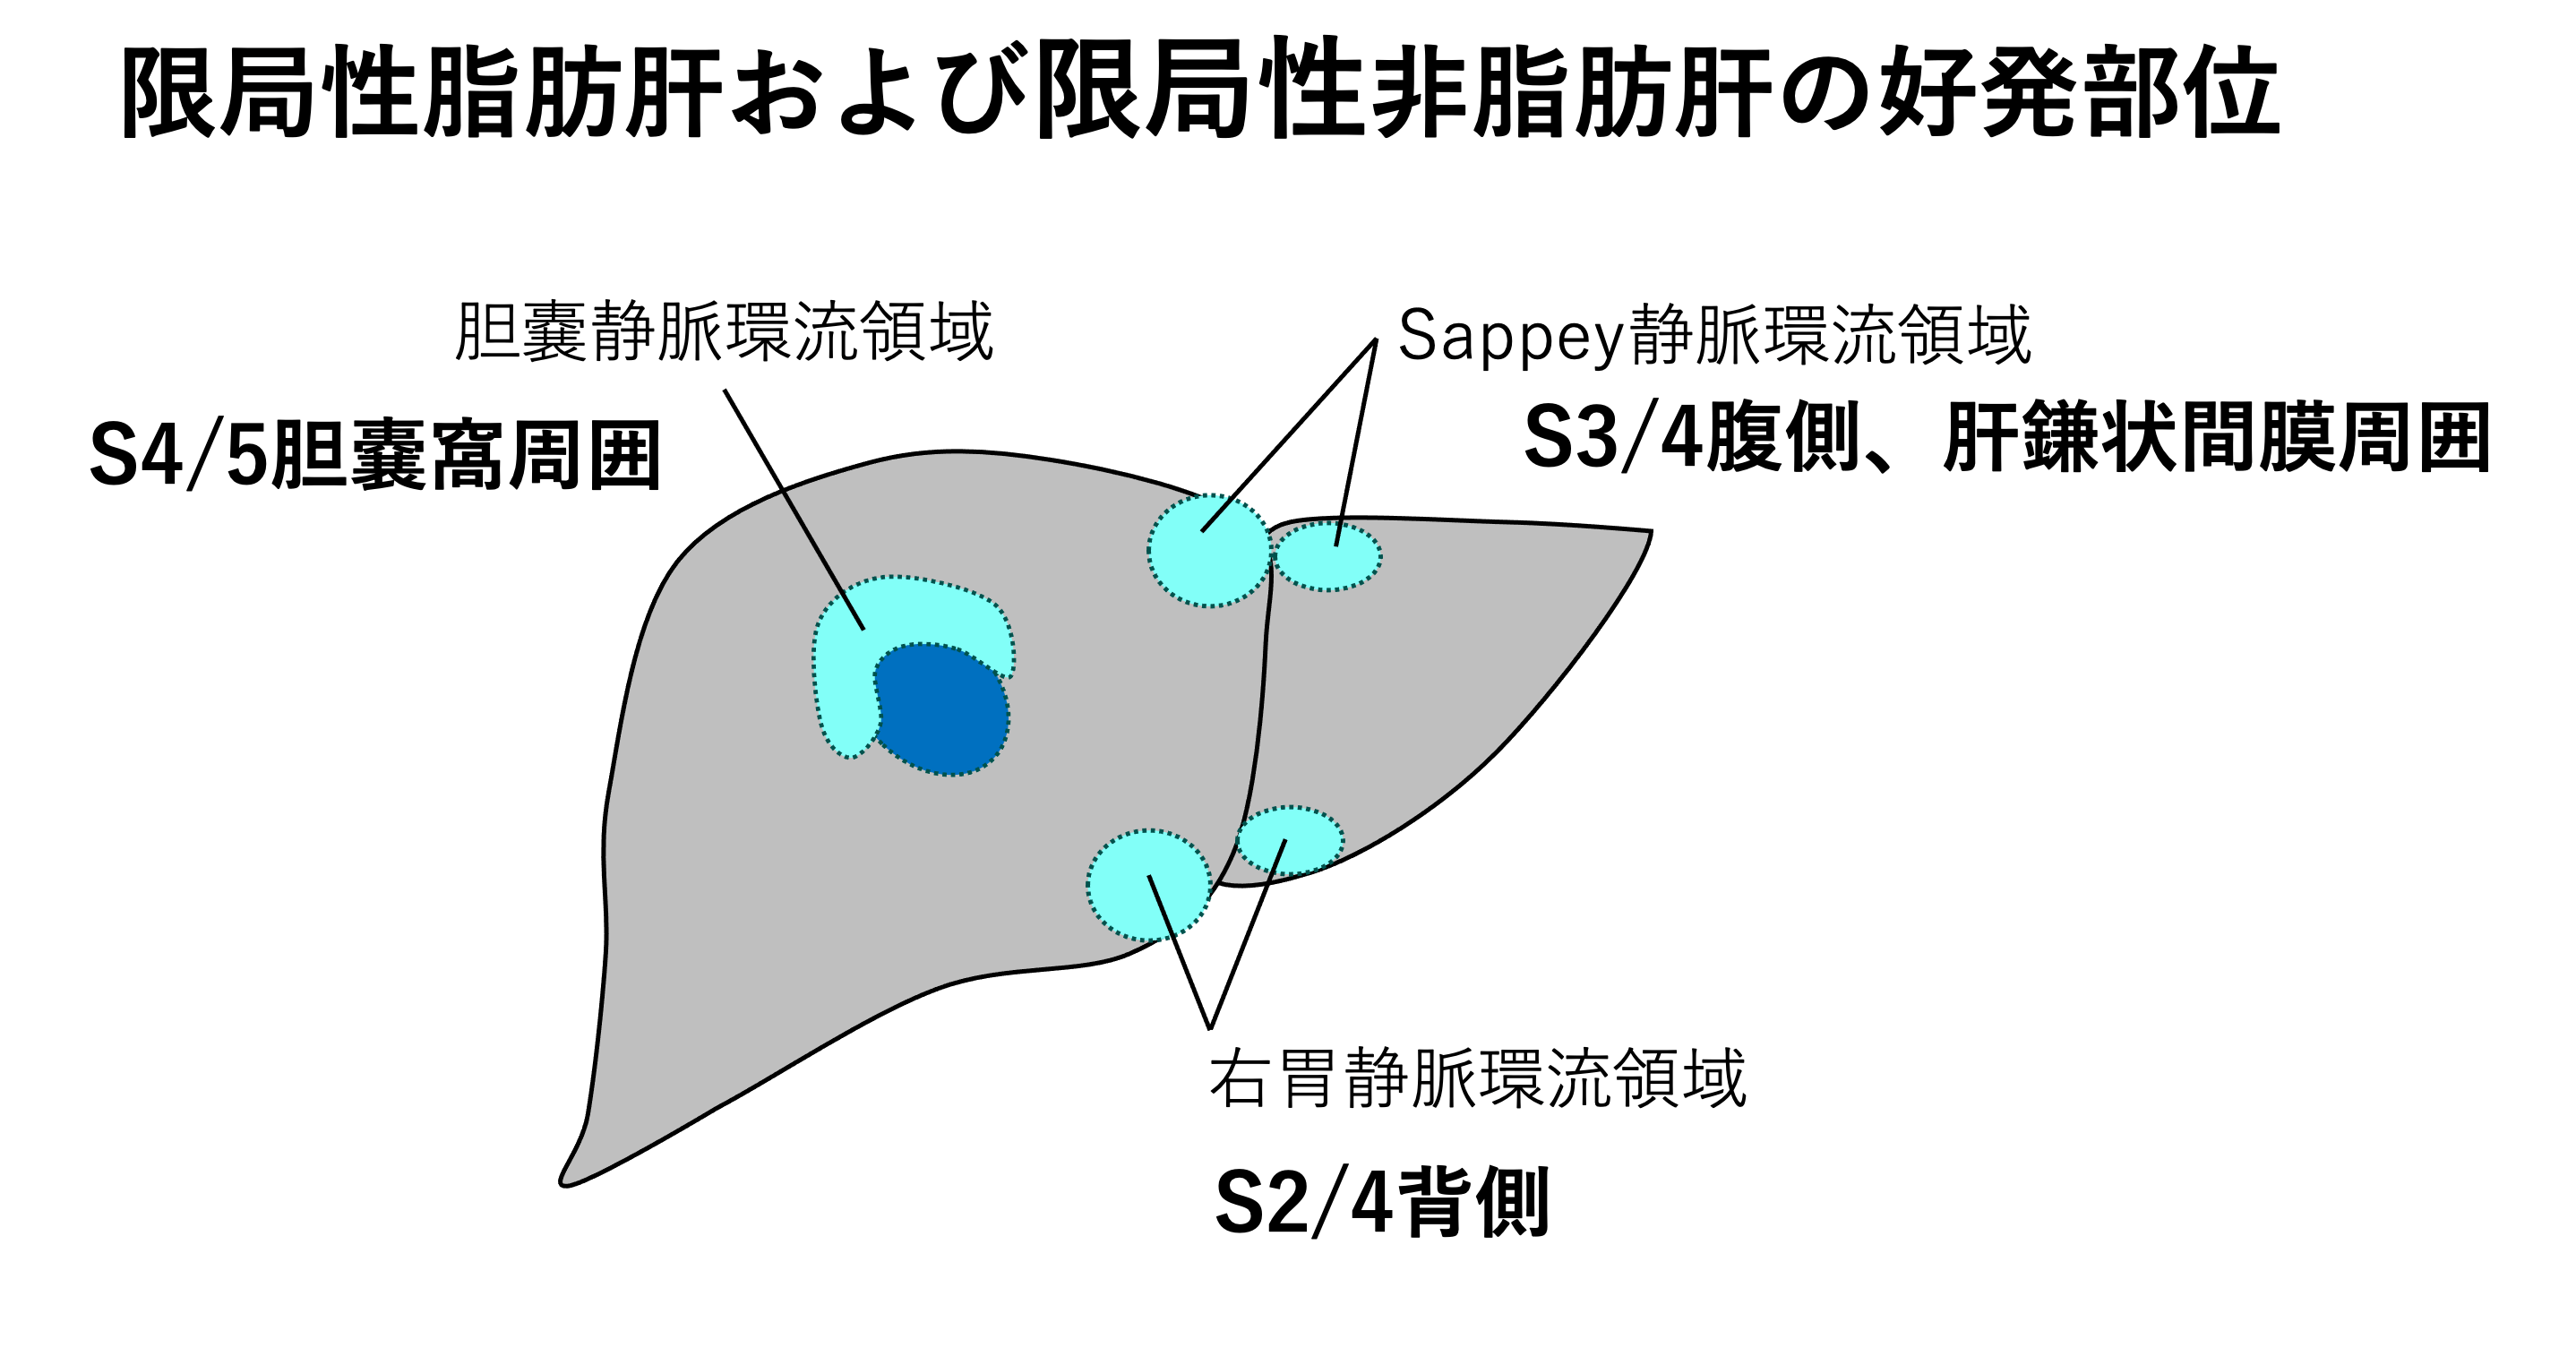

third inflowの灌流領域では、正常な門脈血とは栄養状態やインスリン濃度が異なるため、局所的に脂肪化が進展したり(限局性脂肪肝)、逆に脂肪化が免れたり(限局性非脂肪肝)する現象が生じる。主な流入経路と好発部位は以下の通りである。

- Sappey静脈(腹壁傍臍静脈):肝鎌状靭帯周囲、S3/S4腹側

- 右胃静脈(異所性右胃静脈):S2/S4背側

- 胆嚢静脈:胆嚢窩近傍(S4/S5)